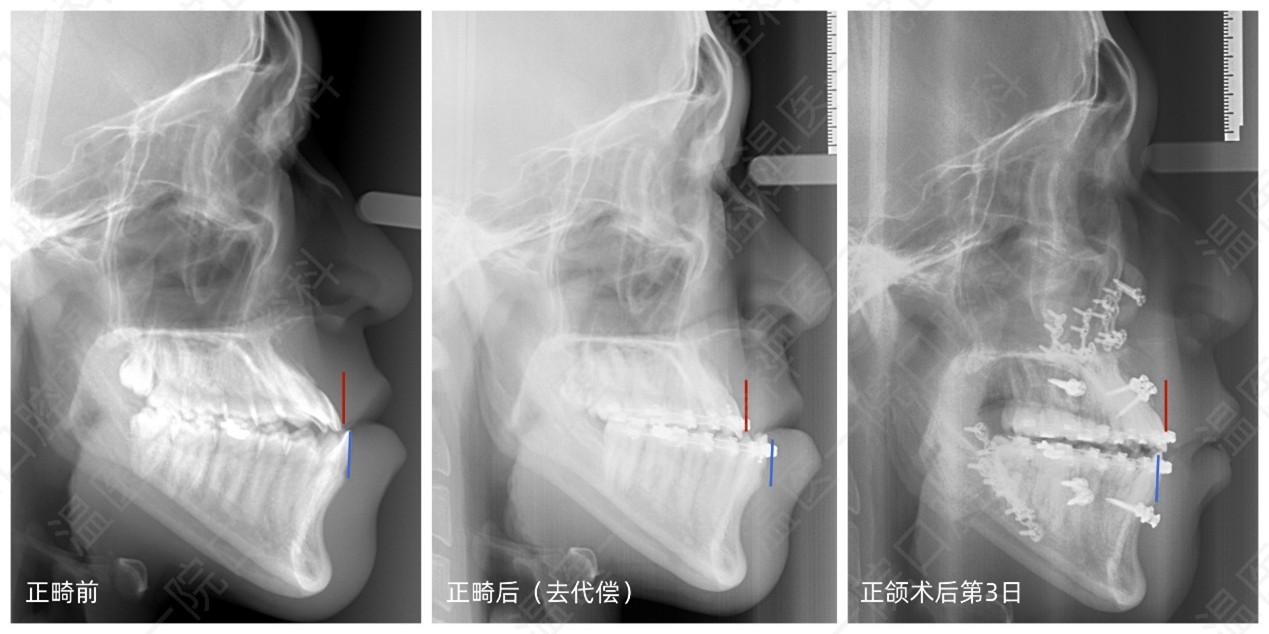

▲患者正畸前后及正颌术后侧位片对照(红线为上颌最前位,蓝线为下颌最前位)

正颌外科作为口腔医学与整形外科交叉的前沿领域,通过截断并重新排列颌骨位置,可一次性解决颌骨畸形导致的咬合功能障碍与面部畸形。本次手术在数字化三维设计方案的辅助下精准控制截骨位置,手术时间及术中出血量较传统术式减少30%,术后患者上下牙列咬合接触面积达到正常人群95%以上,同时面中部凹陷与下颌前突得到显著改善,面部比例协调度提升60%。患者术后第一天即恢复经口进食,咬合稳定,语言功能完全正常。

"过去因为地包天、脸歪,不但不能咬硬的食物,而且很不自信,现在终于能期待着正常咀嚼、正常拍照发朋友圈了。"术后复查时,患者和家属对正畸和手术效果十分满意。据口腔科屠呈威主治医师和刘雪莹主治医师介绍,该患者咀嚼效率从术前的40%提升至90%,面部不对称指数(FAI)由2.8降至1.2(正常值≤1.5),不仅生活质量显著提高,心理状态也明显改善。